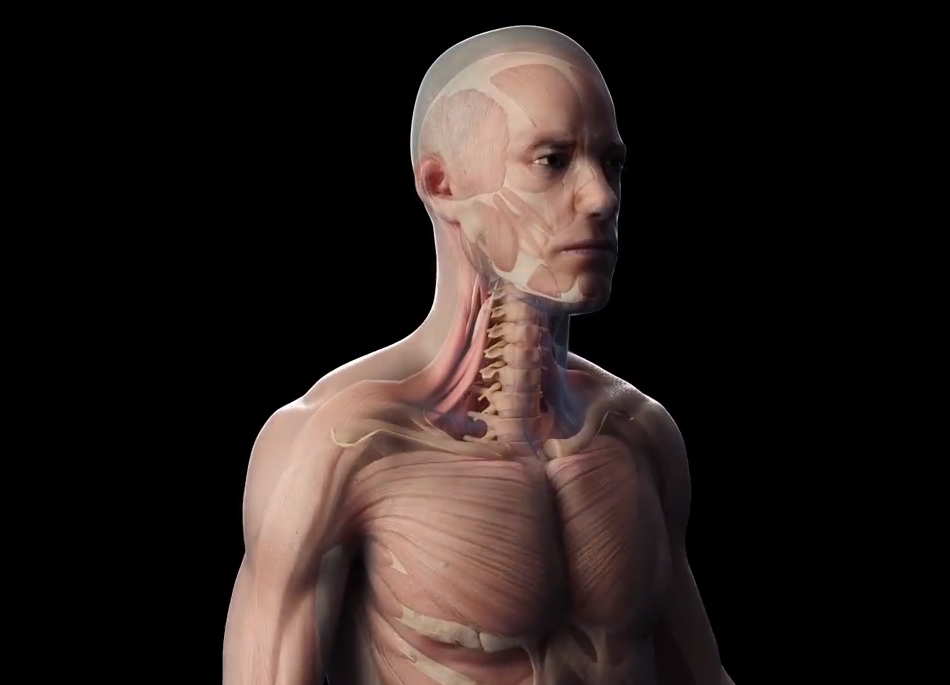

3d Medikal Tanıtım Filmleri - Medikal sektör için 3D ilaç tanıtım filmleri.

3d Modelleme - 3D Modelleme hizmeti. Gerçekç ürün, 3D karakter modelleme.